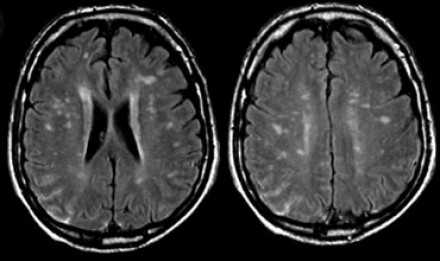

Вернемся снова к первому случаю: на МР-томограммах выявлены очаговые изменения, и сейчас они гораздо более очевидны. Имеет место распространенное вовлечение глубоких отделов полушарий, однако дугообразные волокна и мозолистое тело остаются интактными. Нарушения ишемического характера в белом веществе могут проявляться как лакунарные инфаркты, инфаркты пограничной зоны или диффузные гиперинтенсивные зоны в глубоком белом веществе.

Лакунарные инфаркты возникают в результате склероза артериол или мелких пенетерирующих медуллярных артерий. Инфаркты пограничной зоны возникают в результате атеросклероза более крупных сосудов, например, при каротидной обструкции или вследствие гипоперфузии.

Структурные нарушения артерий головного мозга по типу атеросклероза наблюдаются у 50% пациентов старше 50 лет. Они также могут обнаруживаться и у пациентов с нормальным артериальным давлением, однако более характерны для гипертоников.